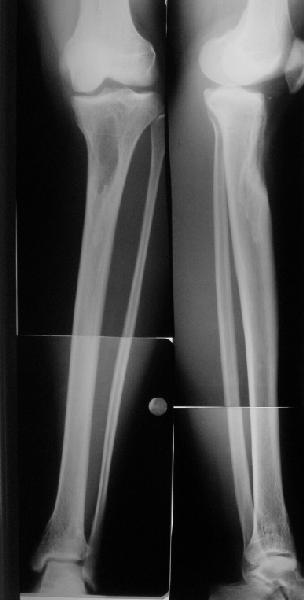

Продолжение обсуждения, начатого в октябре прошлого года (см. здесь) Наконец-то оперировали эту пациентку. Биопсию сделали - опухолевого ничего нет. Пока все участвовавшие в обследовании смежные специалисты и ортопеды сошлись, что это молокальная монооссальная фиброзная дисплазия. 20 марта наложили аппарат, сделали чрескожную остеотомию. К 3 апреля все докрутили. Сегодня заштифтовали. Начальные и итоговые снимки в приложении. Рекурвацию можно было еще немного больше устранить, и чуть кзади сместить диафиз. Но вроде и так ничего выглядит, по сравнению с тем, что было. Комментарии приветствуются.

Есть клиновидный диастаз, контакт основных отломков на очень небольшой площади только в задненаружном отделе. Так что там скорее межотломковая дистракция, а не компрессия.